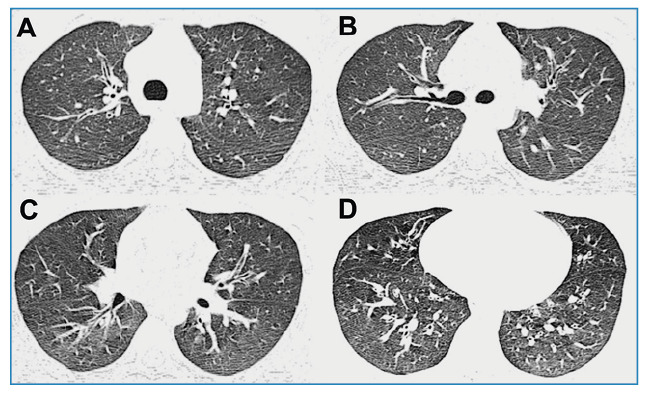

Pertussis in an adult patient.

成人百日咳。